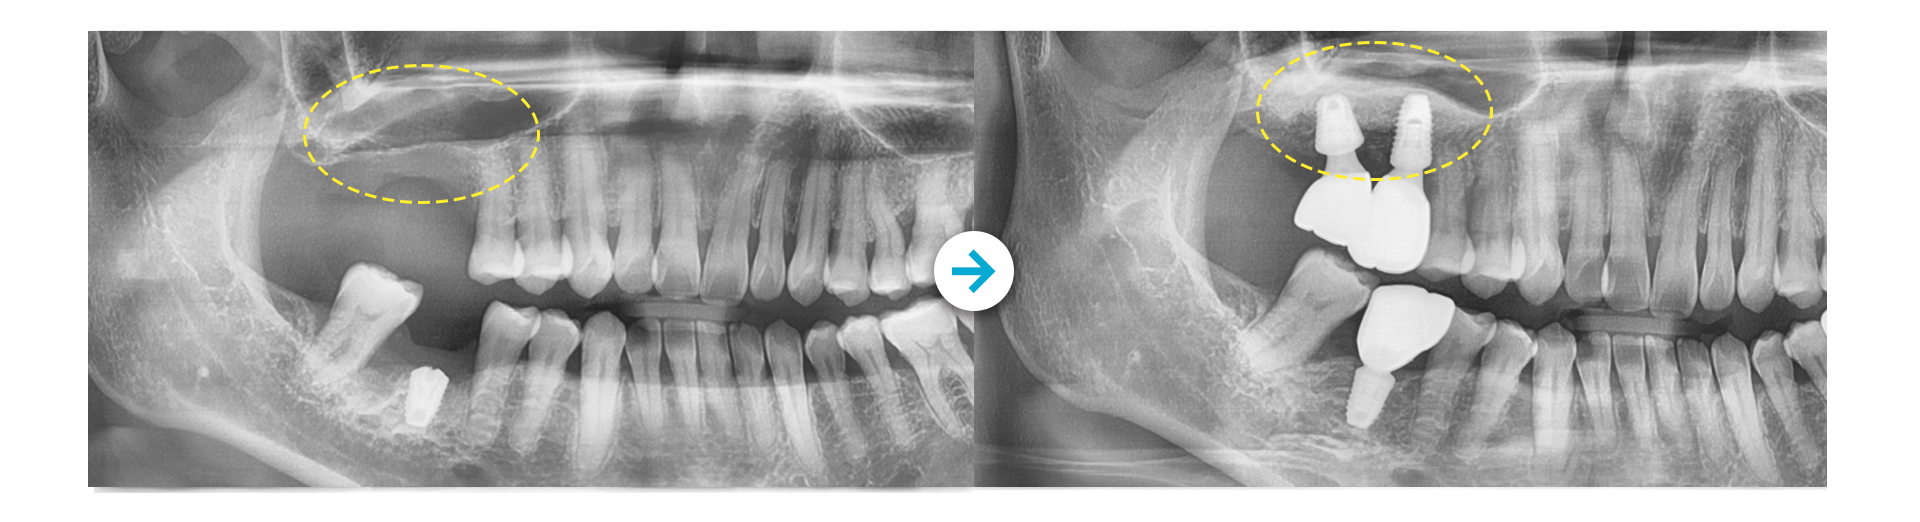

상악동 거상술 후 임플란트 식립

Before 사진 촬영일자: 2017.01.25 /  After 사진 촬영일자: 2017.02.06

Before 사진 촬영일자: 2025.10.27 /  After 사진 촬영일자: 2026.01.07